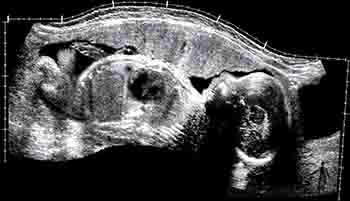

En el quinto mes, los miembros inferiores crecen y adquieren una proporción más armónica. A esta edad la madre percibe los movimientos fetales y es posible auscultar los latidos fetales. La piel está cubierta por una secreción grasosa llamada unto sebáceo o vérnix caseosa. Esta capa grasosa evita la maceración de la piel del feto que flota en el líquido amniótico. En este período se canalizan los canales anal y vaginal, y comienza la migración del testículo. Ecográficamente ya son visibles los riñones y la vejiga urinaria (Figuras 2-21a y b).

Figura 2-21a

Figura 2-21b